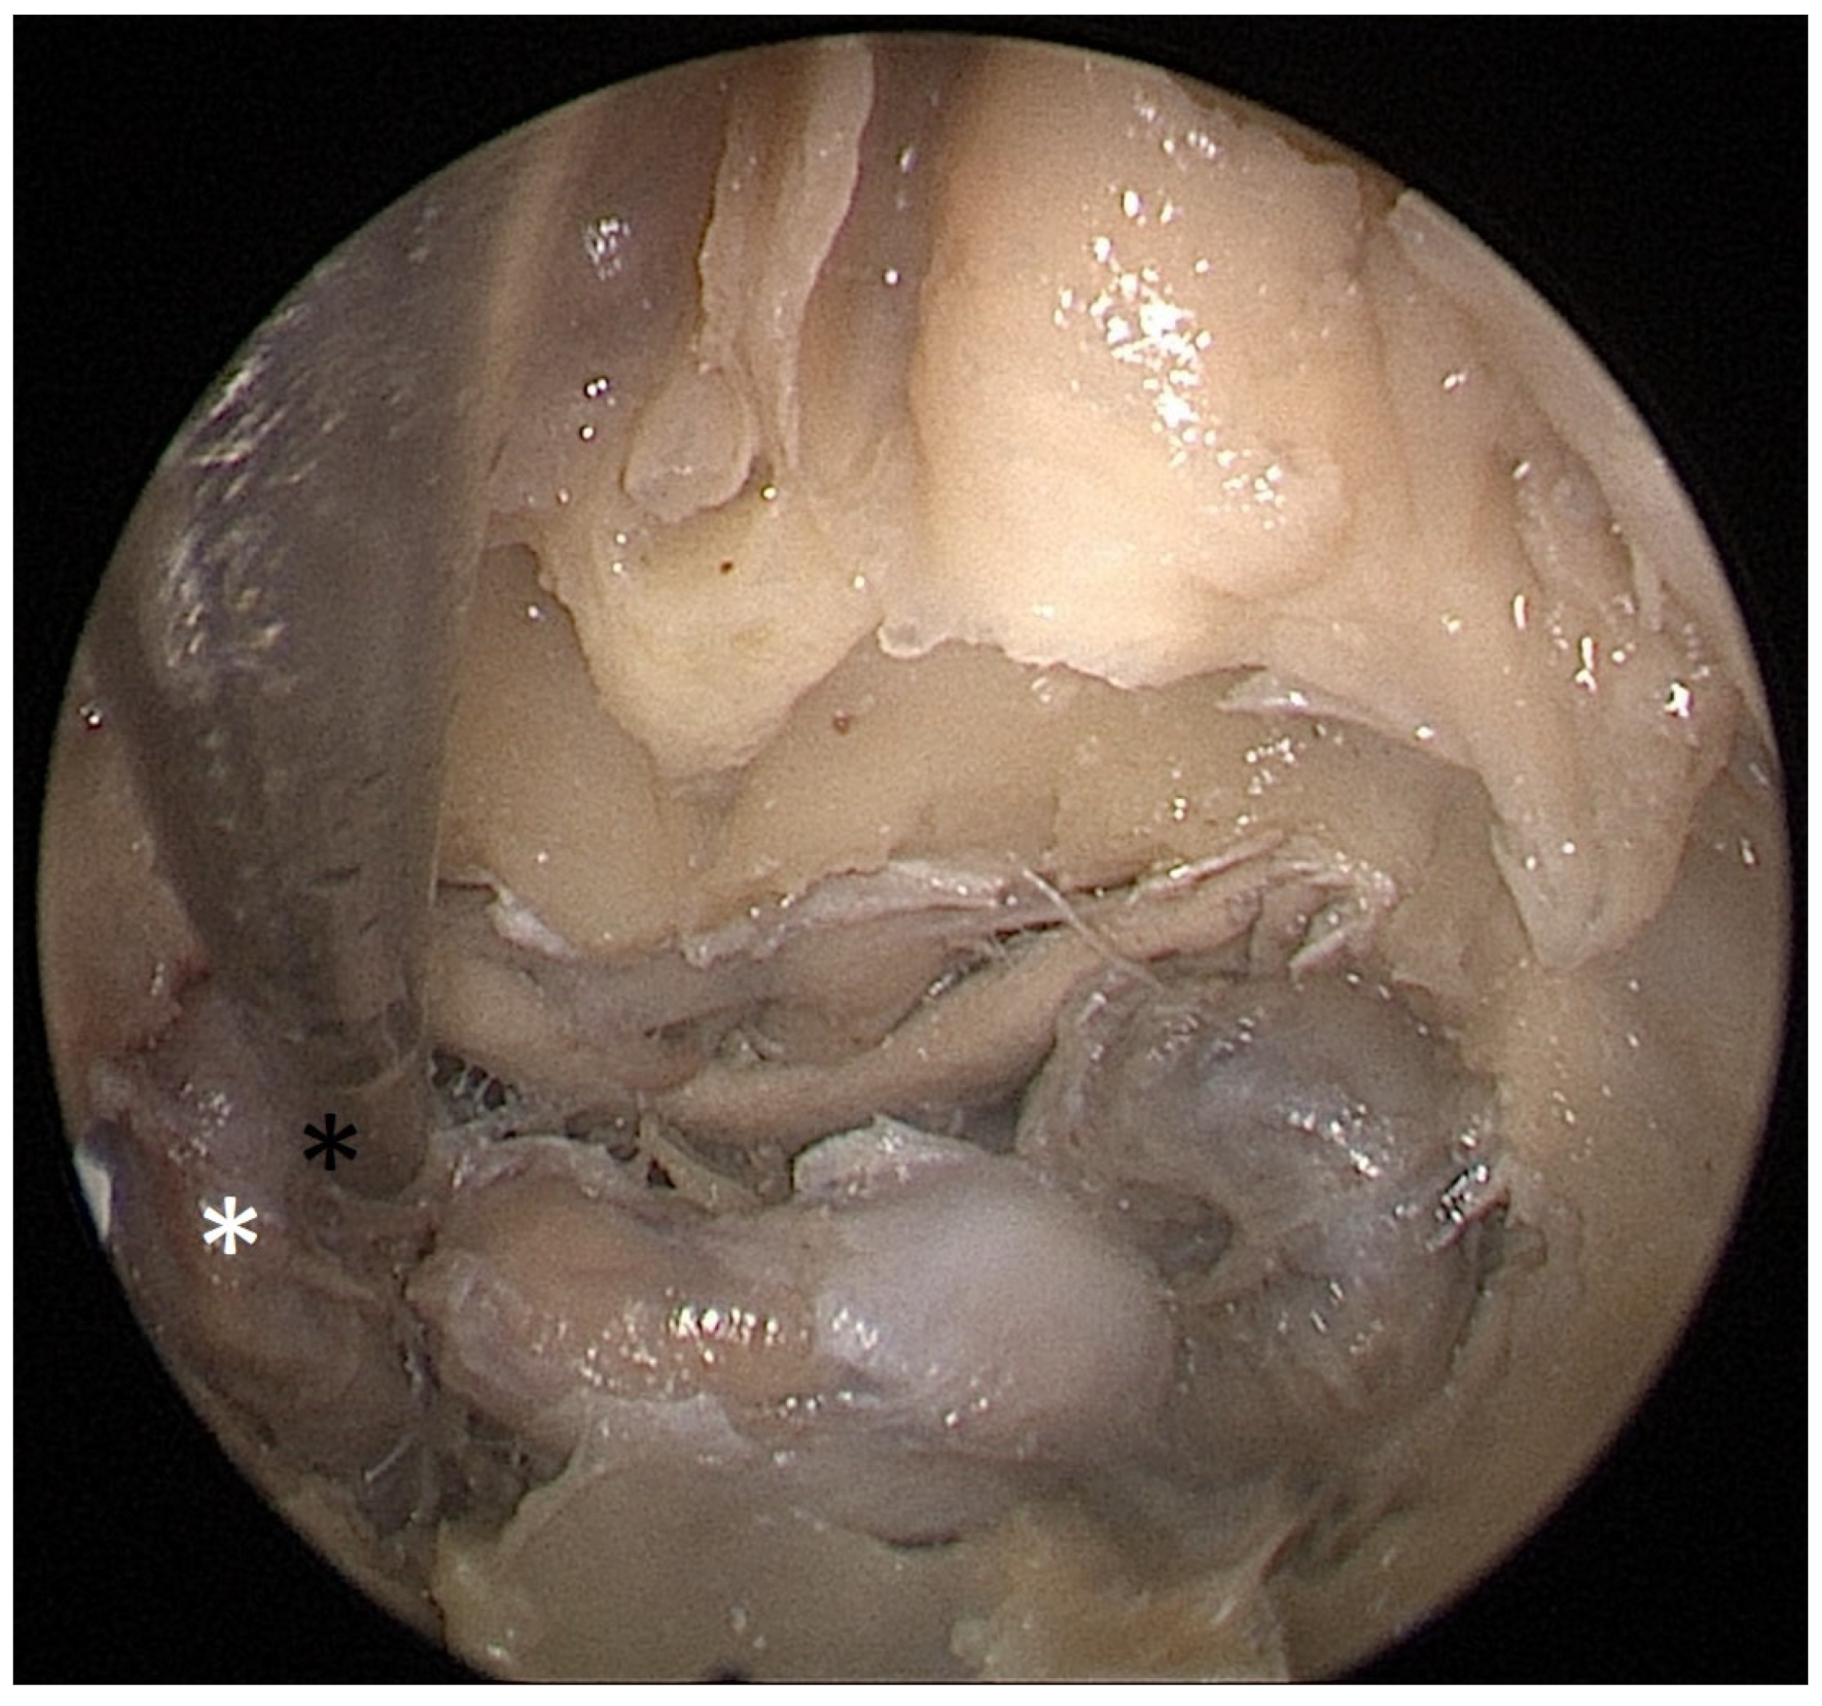

Cadaver pituitary surgery: On each of the two cadaveric heads, we used the paraseptal binostril approach for the sphenoid sinus. A 30° Storz endoscope (Karl-Storz, Austria, Vienna) was used. The head was mounted in a Mayfield cranial stabilization device. The surgery started with a lateralization of the inferior and medial turbinates. The anterior sphenoid wall and ostium to sphenoid sinus were identified. Using the straight suction with a marked scale, 1 cm and 2 cm distances from the anterior sphenoid wall were measured and marked with a scalpel on the posterior part of the septum. Using a scalpel, Kerrison punch, and backbiter punch, a posterior septal resection 1 cm from the anterior wall of the sphenoid was performed. We continued with the wide opening of the sphenoid cavity and resection of the intersphenoidal septum and the full exposure of the posterior wall, both ICAs, and optocarotic recesses (OCR). The posterior wall of the sphenoid sinus and dura were resected to better identify anatomic landmarks, with both ICAs, pituitary gland, chiasma, and optic nerves visible at the end of a resection (Figure 4). The straight suction was inserted into the sphenoid sinus so that the instrument’s tip was in the most lateral position in the sphenoid sinus without infracturing the rest of the nasal septum. A picture was taken in this position to evaluate the most lateral part of the sphenoid sinus that could be reached with a straight instrument with a 1 cm septal resection without infracturing the nasal septum (Figure 5). Enlargement of the septal resection to 2 cm from the anterior sphenoid wall was performed with a backbiter punch and scalpel. The straight suction was inserted into the sphenoid sinus so that the instrument’s tip was in the most lateral position in the sphenoid sinus without infracturing the rest of the nasal septum. A picture was taken in this position to evaluate the most lateral part of the sphenoid sinus that could be reached with a straight instrument, with a 2 cm septal resection, without infracturing the nasal septum (Figure 6).

According to the CT scan measurement on the cadaveric heads, a 1 cm resection of the posterior part of the nasal septum was enough to reach the medial edge of the ICA with a straight instrument, while a 2 cm resection was enough to reach the lateral edge of the ICA. Transnasal endoscopic surgery of the cadaveric heads proved the CT scan findings to be true. A 1 cm resection of the posterior part of the nasal septum was enough for the surgeon to reach the medial side of the ICA without infracturing the nasal septum with the straight instrument. A 2 cm resection was enough for the surgeon to reach the lateral edge of the ICA without infracturing the nasal septum. An approach with a 1 cm resection is sufficient for safe tumor extraction in non-extended cases. The same results were observed in both cadaveric heads. Subjective evaluation of the maneuverability and overview of the operated area was better with a 2 cm resection.

Each head was operated on twice. First, a binostril approach and a 1 cm posterior septal resection were performed. This allowed us, in both cadavers, to comfortably reach the medial part of the carotids bilaterally with straight suction. This resection size would be sufficient for a safe tumor extraction in non-extended tumors. Then, a 2 cm extension of the septal resection was performed. A more extensive resection allowed us to reach the lateral margin of the ICA bilaterally. It also gave us better maneuverability and an overview of the operated area.

Figure 6. Opened sphenoidal sinus, endoscopic view, straight suction (black asterisk) reaching lateral margin of ICA (white asterisk) with 2 cm septal resection.